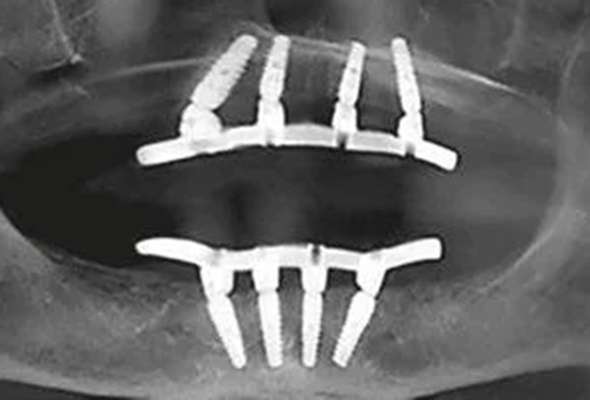

In these cases, Pterygoid Implants can provide an effective solution. Their longer length and unique placement in the pterygoid plates of the sphenoid bone allow them to harness support from the denser bone in this region, thus overcoming the challenge of insufficient bone volume.

Incorporating Pterygoid Implants into the All-On-4 protocol can enhance the stability and durability of the prosthesis, particularly in the posterior region. This combination approach allows for a wider spread of force during chewing, creating a more natural and comfortable experience for the patient. It also reduces the risk of prosthetic failure due to overloading of the anterior implants, ensuring a long-lasting and successful outcome.

Eliminating Cantilever with Pterygoid Implants

A significant advantage of incorporating Pterygoid Implants into the All-On-4 protocol is the elimination of cantilevers. In the standard All-On-4 design, the posterior teeth are not directly supported by implants but are extended beyond the posterior-most implants, forming a cantilever. While this design is generally effective, it can cause excessive force on the anterior implants when chewing hard or sticky foods, potentially leading to complications over time.

With the addition of Pterygoid Implants, these posterior teeth can be directly supported by implants, effectively eliminating the cantilever. This not only improves the distribution of chewing forces but also enhances the stability and strength of the overall prosthesis.

By reducing the strain on the anterior implants, the risk of implant failure is minimized. Furthermore, the elimination of the cantilever allows for a better reproduction of natural tooth function, offering a more comfortable and natural feel for patients. Ultimately, the incorporation of Pterygoid Implants into the All-On-4 procedure results in a more robust and durable full-mouth rehabilitation solution.